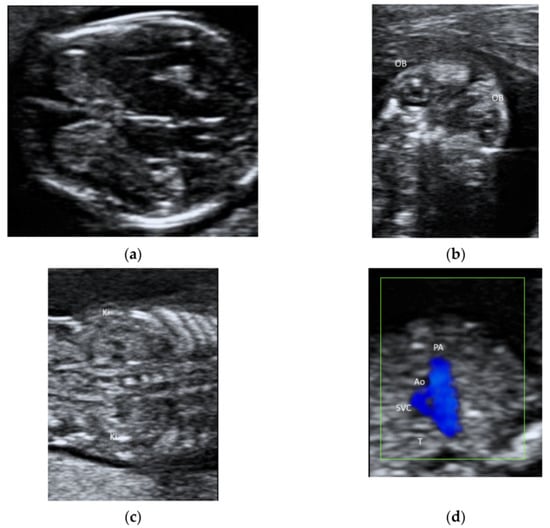

2.1. Fetal Echocardiography and Targeted Neurosonography

5.3. 3D Ultrasound Examination of Face, Limbs, and Other Structures